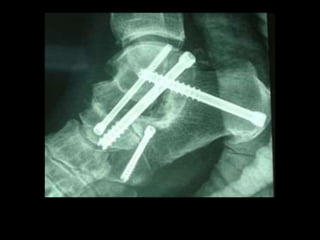

Quirúrgico:

Existen dos opciones válidas para el tratamiento del

estadio II:

• Realizar la reconstrucción del mecanismo funcional y

biomecánico del TTP siempre y cuando esté el tendón

sano y contráctil, mediante tenodesis o transferencias

tendinosas +/- osteotomía medializadora de calcáneo o

la artrorrisis substragalina.

• La otra opción es no actuar sobre el TTP y realizar una

corrección mecánica mediante la osteotomía

medializadora del calcáneo, que también se puede usar

en los grados III y IV en adición a la artrodesis para una

corrección completa.

Quirúrgico En este estadio nos encontramos con un pie

plano valgo-abducto estructurado y rígido cuyo

tratamiento de elección es la artrodesis talonavicular y

subastragalina